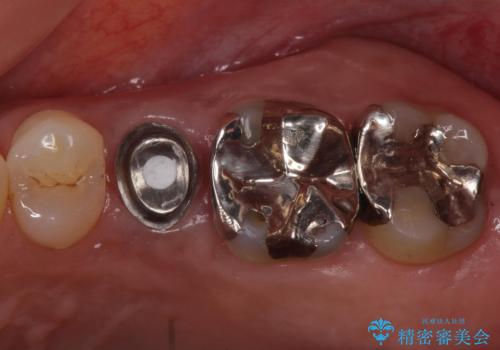

歯茎が腫れる インプラントでの治療

- 40代女性

- 10ヶ月

- 左上5/インプラント:242,000円 骨増生:55,000円 カスタムアバットメント:110,000円 インプラント用仮歯:22,000円 ジルコニアクラウン:121,000円 合計550,000円費用は治療当時の料金となります